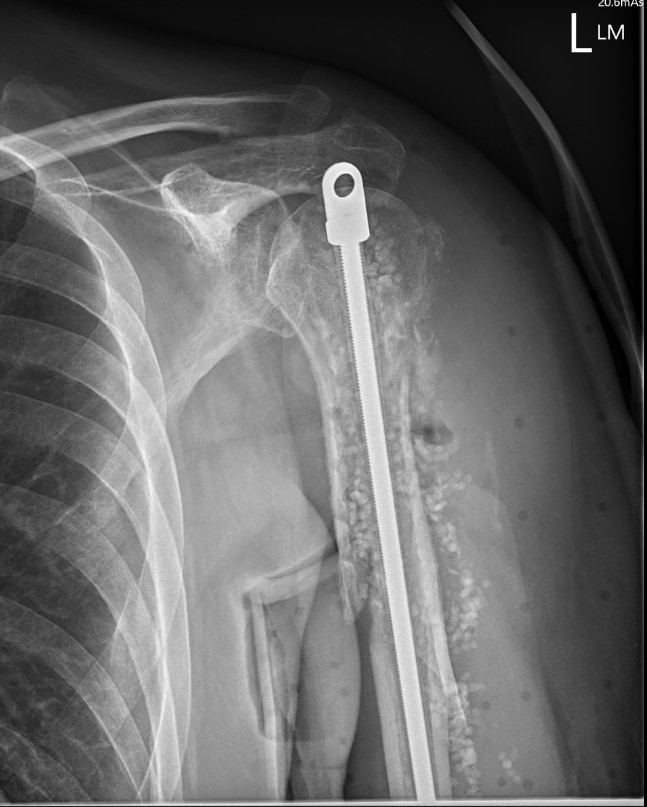

Holstein Lewis fractureHolstein Lewis

Holstein-Lewis JBJS Am 1963

- series of 7 oblique distal third fractures with radial nerve injury

- all were treated operatively

- nerve in fracture gap in 2 / impaled in 1 / severed in 2 / contused +/- in callus in 2

- advised against attempted closed reduction

- risk of contusing nerve between fragments

- advised early open reduction through anterolateral approach

- the radial nerve is closely assoicated with the fracture site and the fracture spike